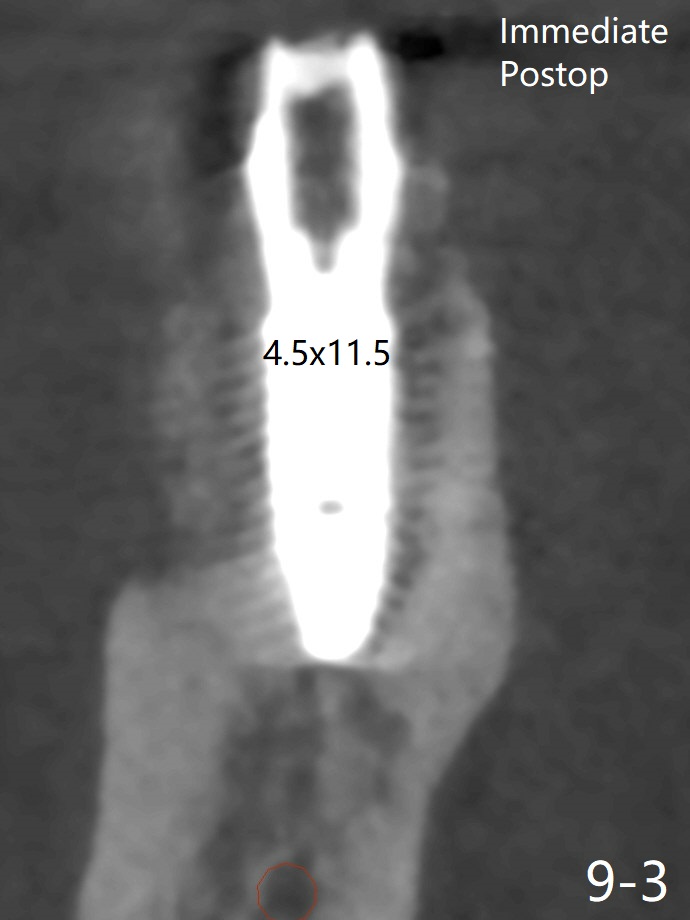

When the tooth #30 is extracted, the gingiva buccal to the septum (S in Fig.1,2 (P: papilla between the mesial and distal roots)) collapses. The latter is fixed with placement of a 4.5x11.5 mm implant (with guide), a 5.2x4(5) mm cemented abutment (Fig.3) and mixture of cortical bone (125μm – 850μm) and cortical/cancellous bone (.5-1 mm) with PRF (sticky bone, B in Fig.4-6). After placement of 2 pieces of PRF membrane over the bone graft, a temporary crown is fabricated to cover the buccal defect (Fig.7 T). Approximately 7.5 mm of the buccal threads are covered by the thick layer of bone graft (Fig.8 B). It is amazing to expect that the bone graft will turn into the buccal plate. It would be better if a narrower implant (4 instead of 4.5 mm) were placed more lingually or there were < 4 mm implant thread exposure (Fig.9). The gingiva reacts to the provisional nicely 7 days postop (Fig.10). The provisional will be removed for modification in 1 month. The patient complains of bad smell from the provisional 2 weeks postop. The provisional is removed. The distal socket (Fig.11 D) is healing, whereas the buccal bone graft (Fig.12 B) seems not have been vascularized. Pedicled flaps (I) should be transferred to cover the buccal bone graft. The margin of the provisional is polished, becomes short, and covered by periodontal dressing, which dislodges 2 days later. One week later, granulation tissue is forming apically with use of oral antibiotic and water jet (Fig.13 *). The bad smell reduces. The superficial loose bone graft changes colar and becomes detached 1 month 10 days postop. The temporary crown with the shortened buccal shelf is reseated for self cleansing or reapplication of PRF if needed (Fig.14).